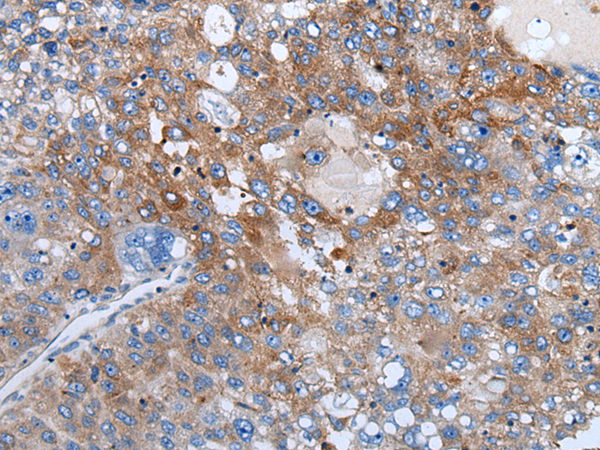

分类: 科研抗体货号: P12880别名: WAP14; dJ447F3.3应用: IHC反应种属: Human